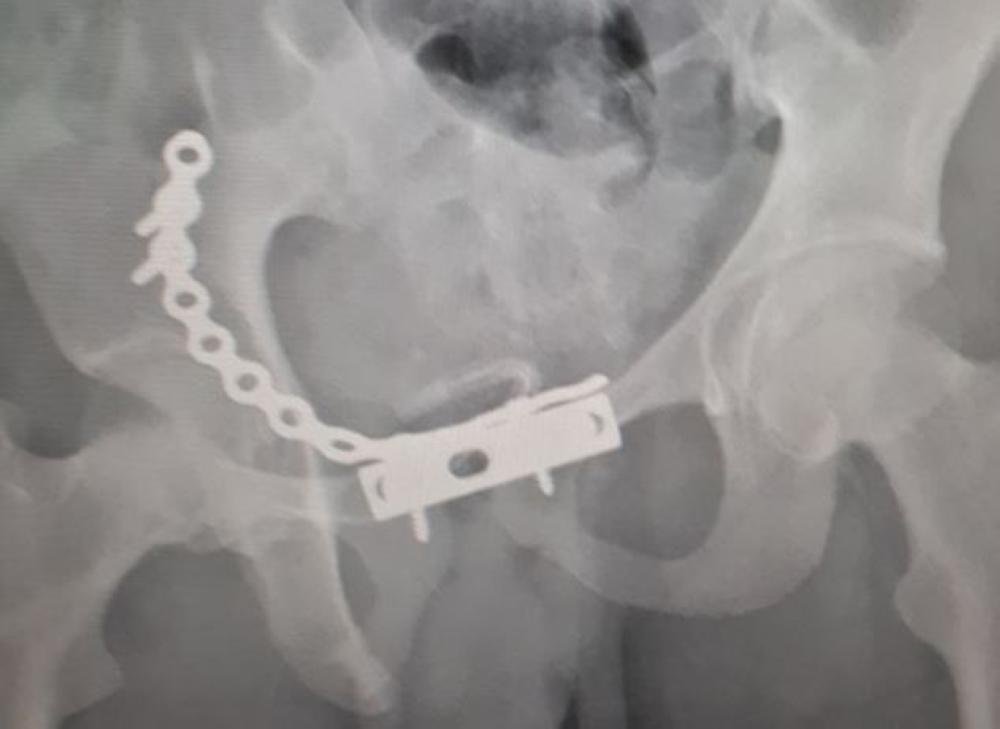

وبعد عرض الحالة على فريق طبي بالمستشفى قرر إجراء تدخل جراحي، وتم بحمد الله إجراء التدخل الجراحي لرد الخلع المفصلي، وتوسع عظام العانة وتثبيت الكسور كافة بواسطة شرائح ومسامير معدنية خاصة لمثل هذه الكسور.